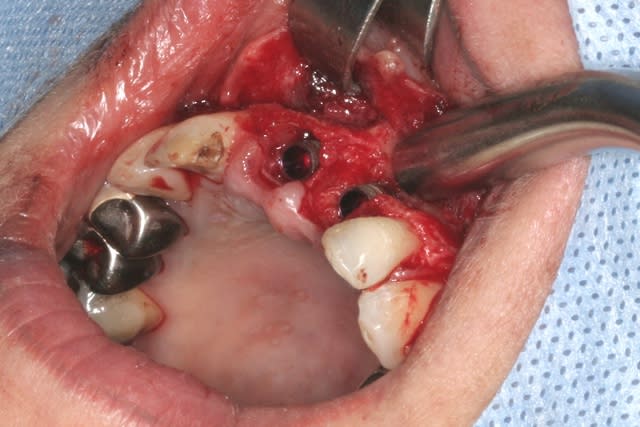

tien, ce matin, extraction de 24/25, curetage méticuleux, forage, comblement du gap, pose des 2 implants qui se sont bloqués à 50Ncm au CA sur les 3 ou 4 mm apicaux, pose des vis de cicat, sutures...35min....tranquille...

un autre cas EII MCI sur 11/21...mais en photos (j'ai aussi la vidéo, faut que je la passe sur youtube)

Purée, tu prends des risques énormes en fourrant ton bio oss puis en vissant les implants dans la masse de bio oss, de un, et sans membraner l'interface pilier implant, de deux...

Je suis peut-être vieux jeu mais c'est, à mon avis, dangereux d'un point de vue bactériologique.

c'est pas la première fois que je fais çà...;-)

et çà me donne plutôt de bons résultats

après tout...le périoste n'est-il pas la meilleure membrane?

par contre il faut veiller à avoir une bonne étanchéité au niveau des sutures...